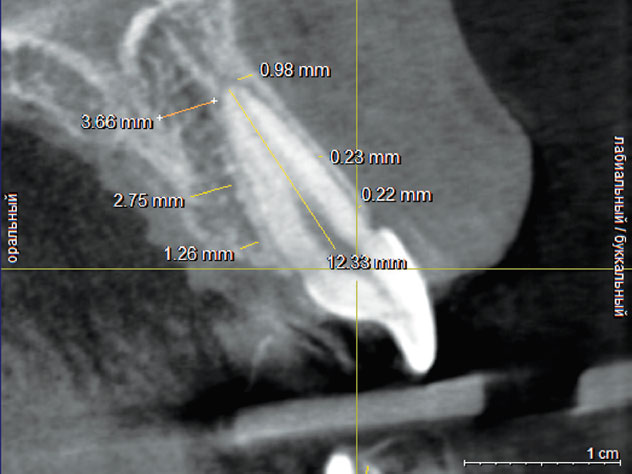

Рис. 3. Измерение толщины губчатой кости с нёбной стороны зуба 1.1

Fig. 3. Cancellous bone thickness measurement in the palatal part of tooth 1.1